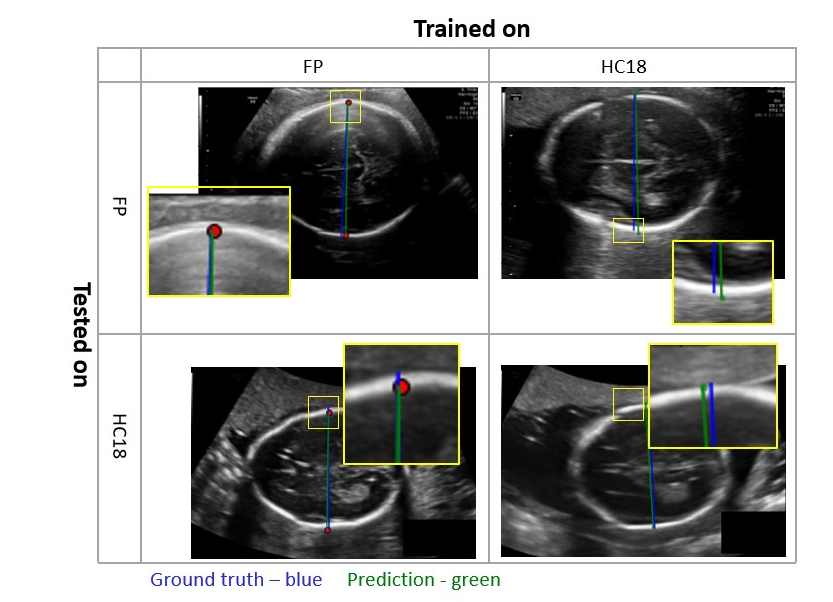

Automating fetal US biometry presents numerous challenges. First, imaging quality varies across different US devices, heterogeneous in overall appearance, particularly regarding gain and zoom. Second, some fetal anatomical structures may become difficult to image with increasing gestational age. Third, anatomical structure position, size, orientation, and appearance present significant variability (Fig. 1). Since the fetus can lie in any of a wide variety of positions, anatomical landmarks can be in orientations that are off the horizontal. Finally, biometric parameters have different geometric characteristics and performed on different SPs, thus each requires its own individual method.

Refer to caption

Figure 1: Fetal biometry variability for the head (red) and femur (blue) SPs. The graphs show (left to right) the distributions of the position (structure center point), size (structure area with respect to image area) and orientation (structure angle with respect to horizontal plane). Sample US image inserts illustrate the distribution.